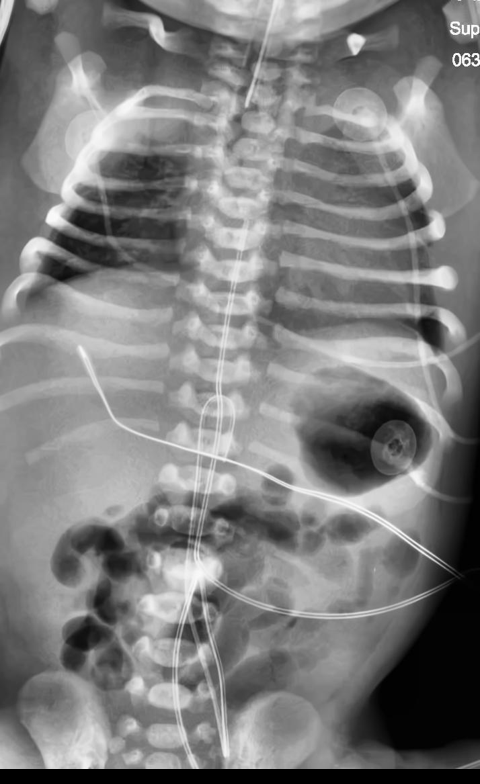

Automated catheter detection is a challenging task. Although most catheters have a radiopaque strip to facilitate detection, the strip may become less apparent depending on the projection angle. Catheters maybe confused by other similar linear structures like ECG leads and anatomy including ribs. Additionally, portions of catheters can be occluded by anatomical structures given that radiographs are a 2D projection of a 3D structure. For example, when a NGT is placed within the oesophagus, the catheter itself becomes less apparent due to the high density of the adjacent vertebrae. Finally, the number and type of catheters that could possibly appear in pediatric X-rays are unknown a priori. The catheters may be intertwined with each other thus making simple line tracing methods fail. Figure 1 gives three sample pediatric X-ray images with some common catheters highlighted in different colors.

To alleviate this annotation problem in catheter detection, we proposed to use X-ray images with simulated catheters by exploiting the fact that catheters are essentially tubular objects with various cross sectional profiles. To be more specific, a synthetic 2D projection of a catheter is generated by first simulating a horizontal catheter profile and then using it as a brush tip to draw along a B-spline path. This generated catheter is then composited with an X-ray image serving as the training data. Another contribution of this work is a segmentation network that can inherently take into account multi-scale information. This network adopts a UNet-style form and contains a recurrent module that can process inputs with increasing scales111Our code is available at https://github.com/xinario/catheter_detection.git.. We have empirically shown that by iterating through the scale space of the input image, higher recall is achieved as compared to using a single scale. Details about the methods are discussed in Section 3. Three sample detection results are shown in Figure 1.

The test dataset is collected locally and only contains frontal chest-abdominal X-rays from patients < 4 weeks old. This is the most common radiograph obtained to confirm placement of catheters such as UACs and UVCs in neonates. Currently, the test set has 35 fully labeled images with different catheter types with sample images previously shown in Figure 1. All the annotated catheters (lines excluding ECG leads) are treated as the same class in the detection.

There are certain situations where our proposed method would fail. Figure 7 (a) and (b) show a partially detected NGT. This mostly likely resulted from the decreased visibility of the radiopaque strip. Figure 7 (a) also shows another failure situation where the inferior portion of the UVC is occluded by the abdomen. (c) shows the case of a falsely detected unidentified line and (d) shows part of the lateral aspect of the rib cage falsely identified as a catheter.